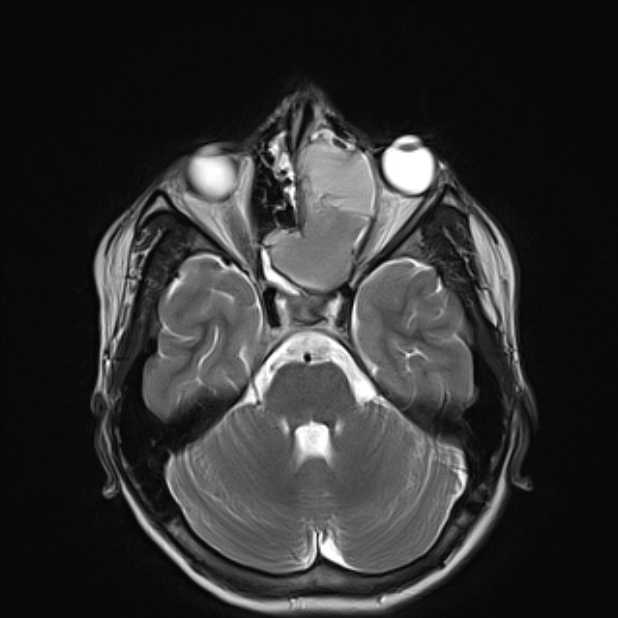

FIGURE 31-5 Basal encephalocele.A, A sagittal T1-weighted image shows callosal agenesis with a tiny lipoma (arrow). A large defect in the basisphenoid is seen. Note the apparent absence of the pituitary, floor of the third ventricle, and optic pathways. B, A high-resolution sagittal T2-weighted image shows the pituitary-hypothalamic structures (arrow) and optic pathways are contained within the encephalocele.